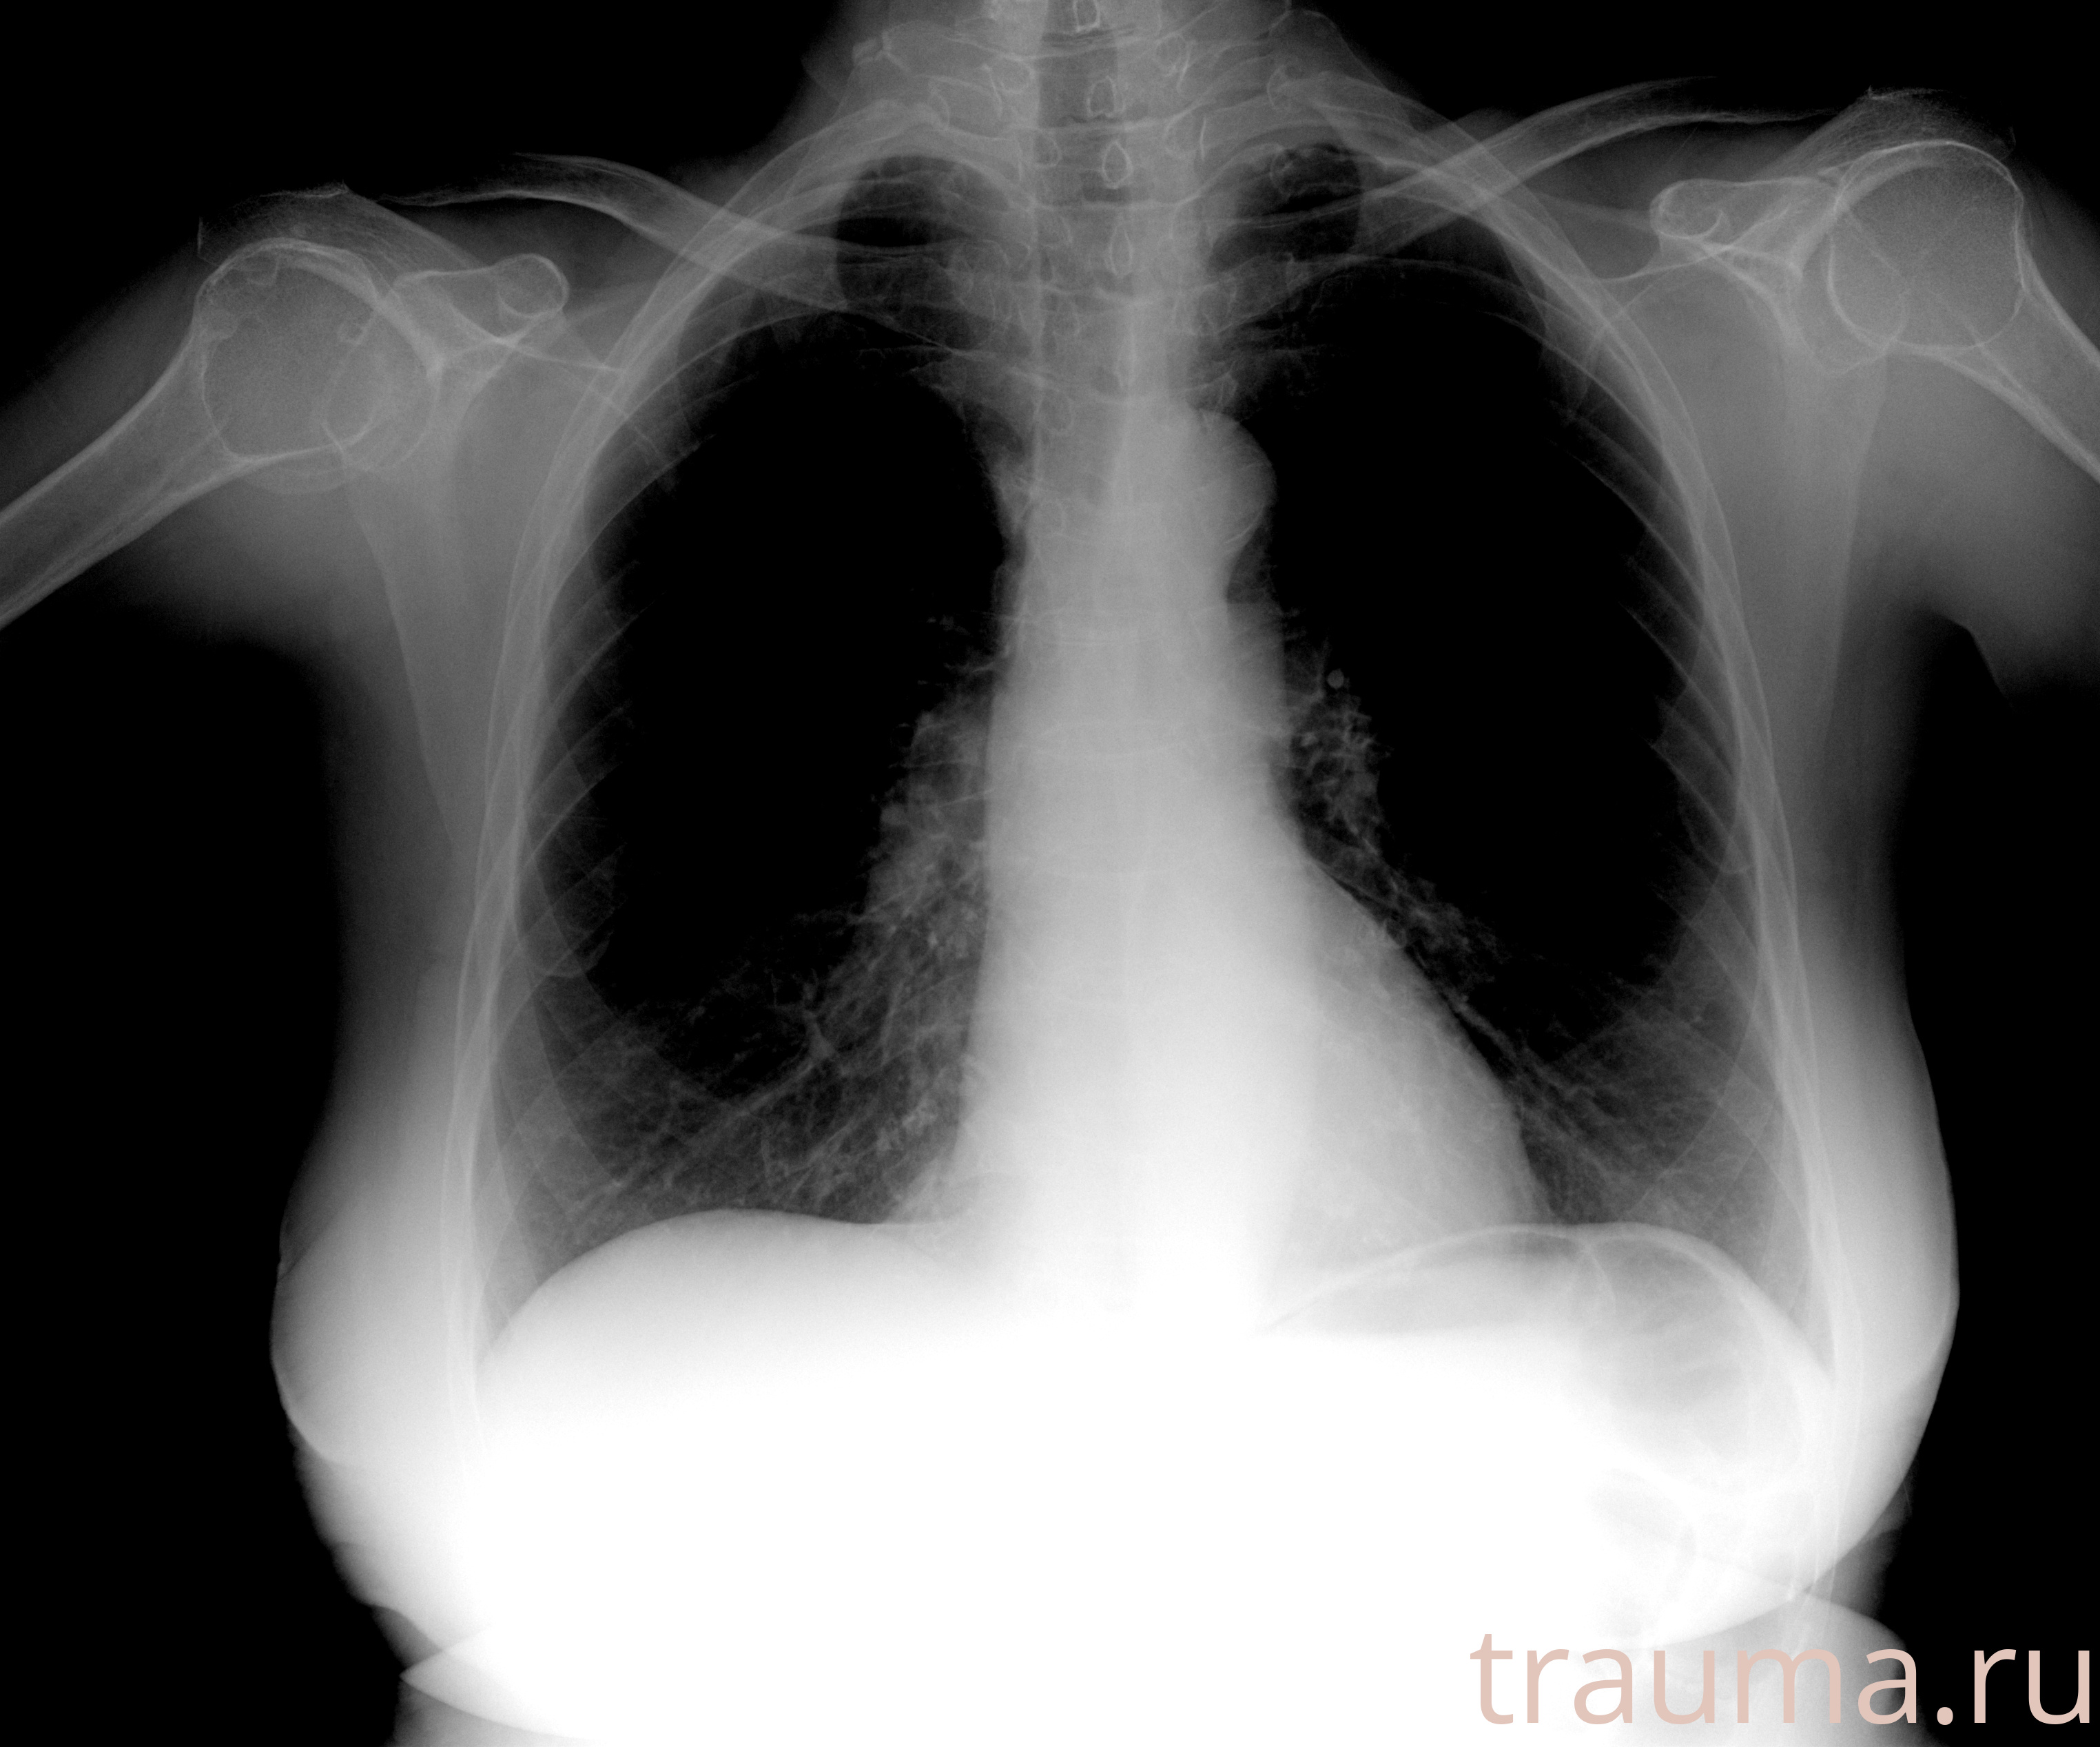

Рентген на дому: по вашему адресу приезжает врач-рентгенолог, травматолог-ортопед с мобильным рентгеновским аппаратом, проводит диагностику травмы или заболевания, делает необходимые рентгенограммы, дает рекомендации по дальнейшему лечению. Получить качественные снимки в домашних условиях возможно благодаря уникальной методике, разработанной МосРентген Центром для института  Склифосовского

при переломе шейки бедра и пневмонии от компании МосРентген Центр - партнера Института имени Склифосовского